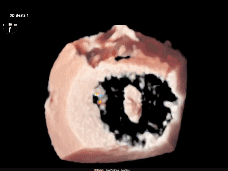

3D下组织桥稳定

3D下上彩

术后平均压差为4mmHg